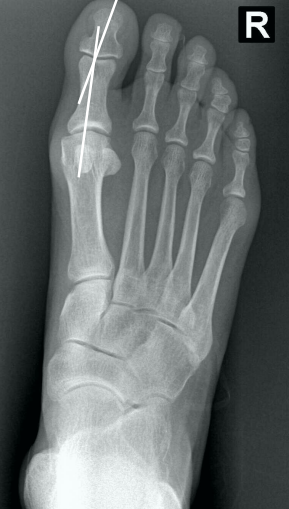

# Hálux valgo - No tratamento cirúrgico, o que corresponde o **procedimento de Akin** e quais as suas principais características?

- **Osteotomia de fechamento medial da base da falange proximal** - Isolado no tratamento do hálux valgo interfalângico - Raramente utilizada isoladamente - **Pode complementar a correção de um procedimento metatarsal sem comprometer a articulação (5 a 10º adicionais)** - Manter a cortical lateral íntegra agrega estabilidade - **Corrige 8º par cada 3 mm de cunha ressecados**

# Hálux valgo - Quais as principais **indicações** (2) da **osteotomia de Akin** (fechamento medial da base da falange proximal)?

- Hálux valgo interfalângico - Correção adicional após outra osteotomia

# Hálux valgo - Quais as principais **contraindicações** da **osteotomia de Akin** (fechamento medial da base da falange proximal)?

- Artrite Reumatóide - Artrose de moderada a grave na metacarpofalangeana - Ângulo intermetatarsal > 13° - Ângulo de valgismo do hálux (metatarsofalângico) > 30° - Subluxação do sesamóide medial > 50% - Fise aberta